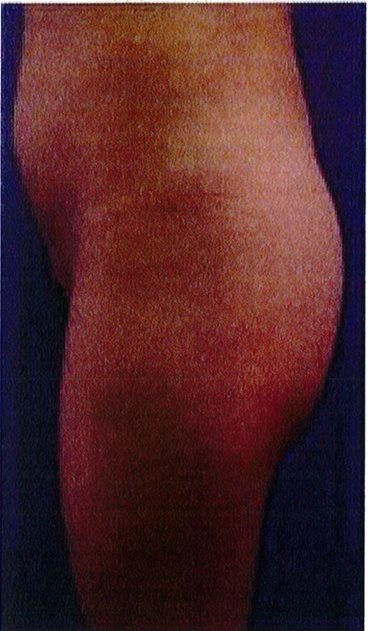

Hình. 19. . (A) Hình anh trước và (B) và sau phẫu thuật làm đầy mông của bệnh nhân chùng da vùng mông tương đối nhiều. Bệnh nhân được đặt khối implant dưới cân thể tích 330 mL ở hai bên.

Bệnh nhân 52 tuổi xuất hiện chùng da vùng mông (mức độ nặng), mong muốn giải quyết vấn đề này đồng thời tăng kích thước vòng ba. Hai khối anatomic implant

thể tích 330mL dạng silicone được đặt ở dưới cân cơ mông lớn.Hậu phẫu đánh giá thấy giảm thời gian hồi phục (Hình 19).